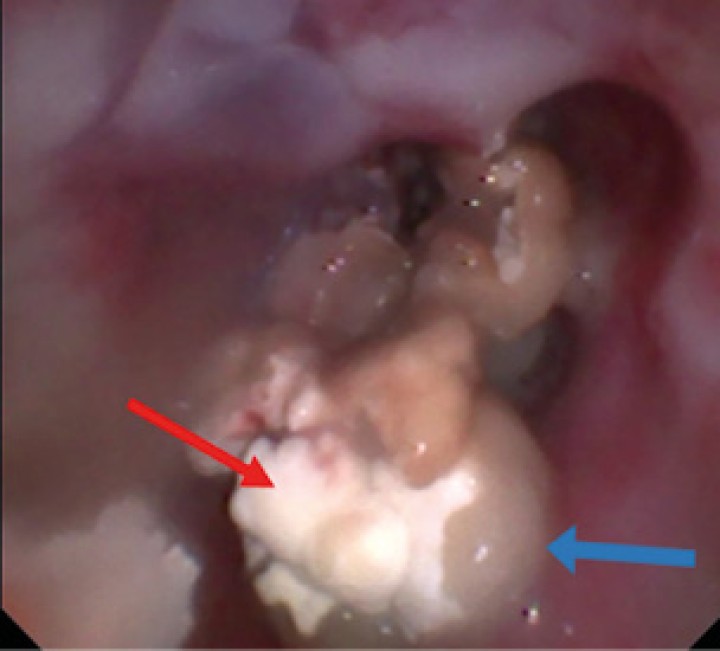

Se procedió a realizar una TC de cráneo (posicionamiento en recumbencia esternal, con 1,25 mm de corte, adquiriendo imágenes pre y postcontraste con contraste yodado Iohexol (Omnipaque 300 mg/ml, GE Healthcare Bio-Sciences, Florida) 400 mg/kg, con algoritmo de reconstrucción de tejido blando y hueso, General Electrics Healthcare, 4 cortes, España, Madrid). En la TC se observó en la cavidad nasal izquierda una moderada destrucción de turbinetes nasales con severo engrosamiento de la mucosa nasal y presencia de tejido blando anómalo (Fig. 1A), sin presencia de masas o cuerpos extraños, ni afectación de la lámina cribiforme. Dichas lesiones se extendían al seno frontal izquierdo (Fig. 1B). A continuación, se realizó una rinoscopia (fibroscopio 5,9 mm, FujiFilm, España, Madrid) donde se observó en la cavidad nasal izquierda múltiples placas de color blanquecino con aspecto caseoso/algodonoso adheridas a la mucosa nasal con eritema y congestión asociados (Fig. 2), junto a la destrucción moderada de los turbinetes, mostrando un aspecto cavitado. La cavidad nasal derecha no presentó alteraciones. Se tomaron muestras de tejido (placa fúngica y mucosa adyacente) para cultivo y análisis histopatológico. En el cultivo se obtuvo un crecimiento de Aspergillus fumigatus, y en los resultados de la biopsia de la placa fúngica se observó un tejido eosinofílico con abundantes hifas septadas, mientras que en el tejido adyacente se evidenció una mucosa erosionada y ulcerada con abundantes neutrófilos y macrófagos con hifas fúngicas esporádicas.

Imagen de la rinoscopia en cavidad nasal izquierda (meato nasal). Se pueden observar placas fúngicas de color blanquecino (flecha roja) y secreción mucopurulenta (flecha azul). Debido a la destrucción de los turbinetes presenta un aspecto más cavitado.